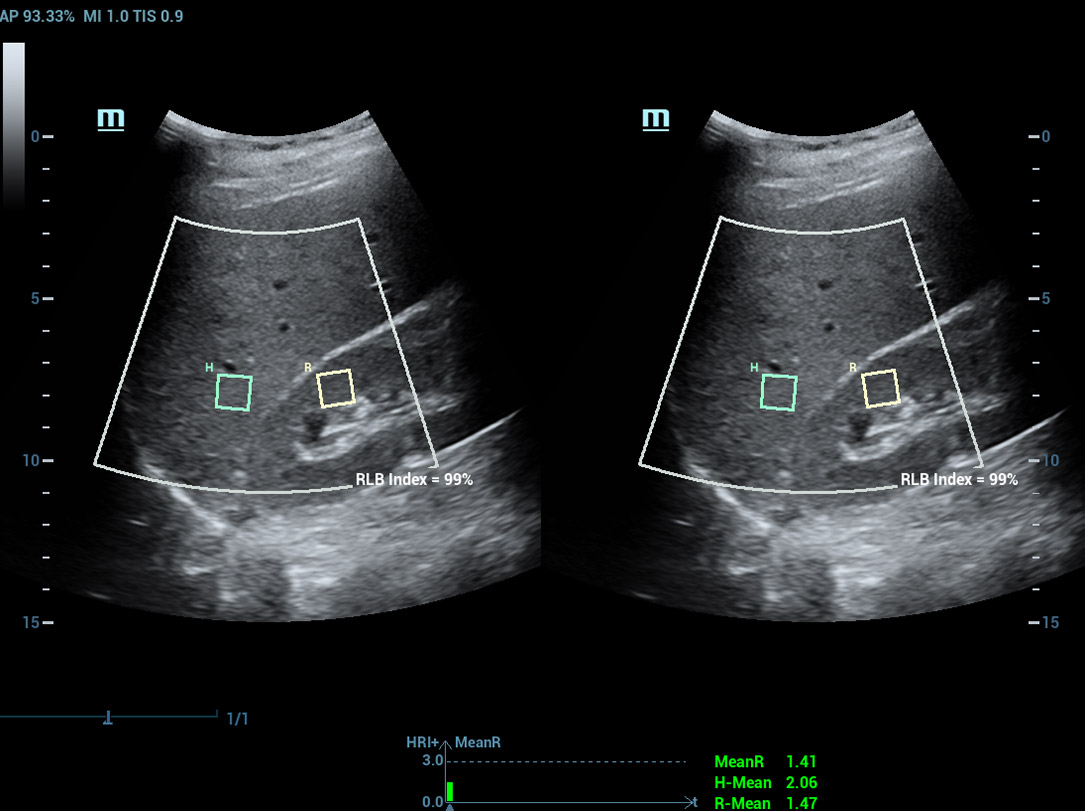

Analisi di laboratorio multiparametriche del fegato grasso

Le analisi di laboratorio multiparametriche del fegato grasso forniscono molteplici strumenti di analisi quantitativa basati su diverse tecnologie acustiche. Consentono di effettuare l'analisi quantitativa della steatosi e migliorano la sensibilitĂ della rilevazione del fegato grasso in fase precoce.